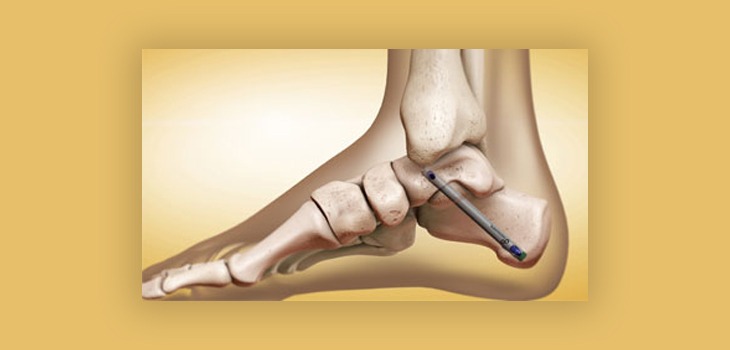

In a global Ankle Fusion Nail procedure, the surgeon first prepares the ankle joint for fusion by removing cartilage surfaces from the tibia and talus bones. The hollow medullary canals of both bones are then reamed out to accept the intramedullary nail. Specialized global ankle fusion nails feature a curved design that allows them to span the ankle joint internally once inserted. Some nails even have built-in compression capabilities.

The nail is manually inserted or driven into place using an insertion jig and hammer. Proper alignment and leg rotation are crucial to ensure the bones are fused in correct position. Once fitted, the nail links and stabilizes the tibia and talus bones internally. This allows bony surfaces to heal together as one unit (arthrodesis) without relying on external hardware. The nails may be left in place permanently or later removed depending on the surgeon’s preference and individual patient factors.